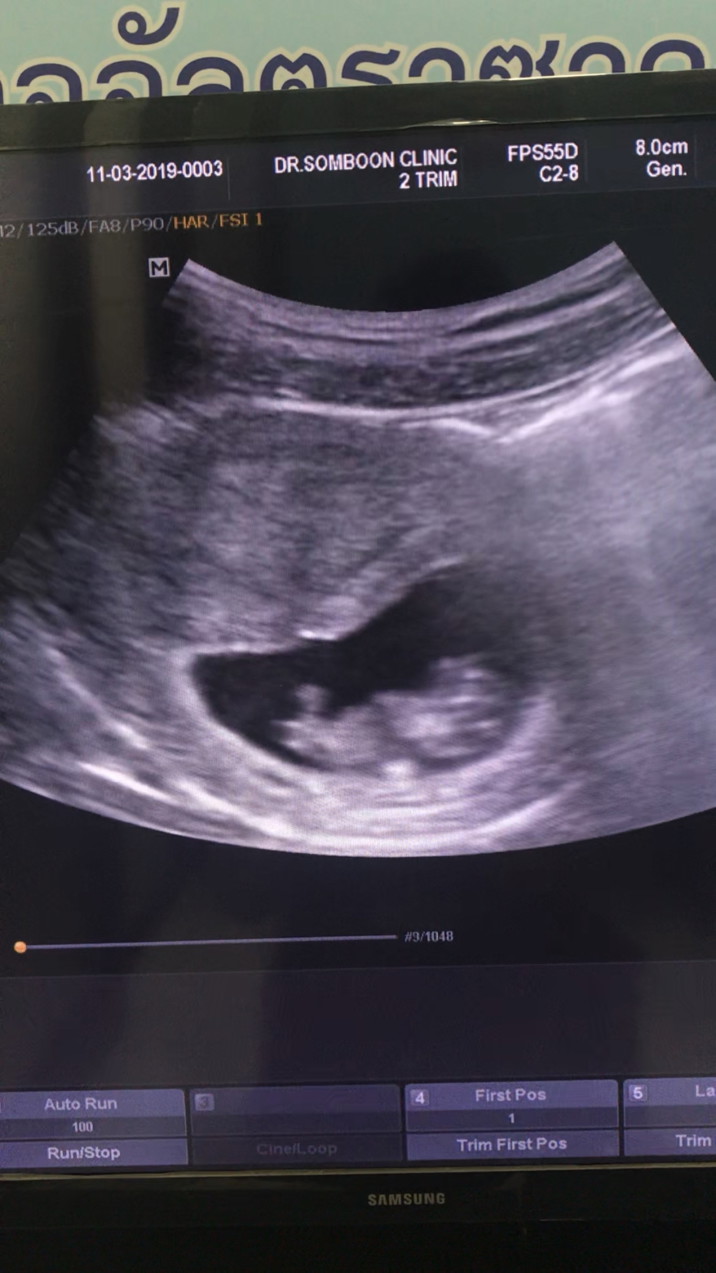

11 wค่ะ